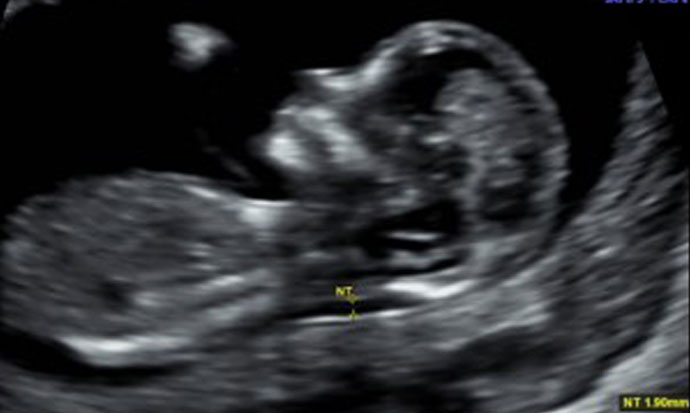

Generally, pregnant women will receive two ultrasound scans at their local NHS hospital; one at around twelve weeks and one at around 20 weeks. The 12 week scan is used to accurately date the pregnancy whereas the 20 week scan is important for ensuring the baby is developing normally.

Three dimensional ultrasound uses exactly the same harmless sound waves as traditional (2D) scans, except they are sent from multiple angles. When the waves reach the baby they are reflected back to a sophisticated computer system which uses the echoes to construct a 3D image of the baby in the womb. In 4D ultrasound scanning, this process is done in real time so that the baby can be seen moving and this can be captured as a video.